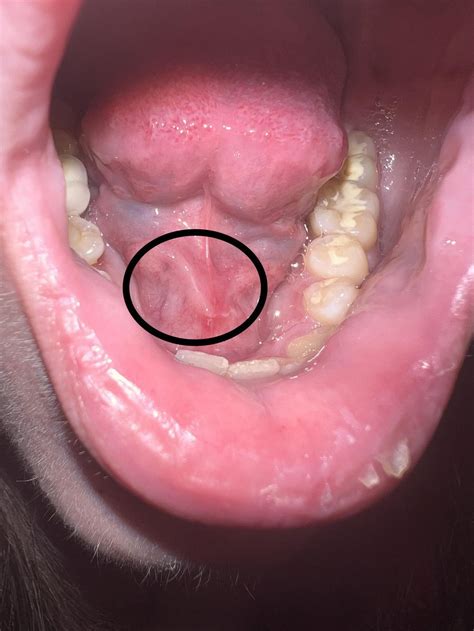

Oral skin tags, also known as fibromas or acrochordons, are small, benign growths that can appear on the skin inside the mouth. These growths are typically flesh-colored or slightly darker and can vary in size from a few millimeters to several centimeters. While oral skin tags are generally harmless, they can sometimes cause discomfort or interfere with daily activities such as eating or speaking. Understanding the causes, symptoms, and treatment options for oral skin tags is essential for managing this condition effectively.

Oral skin tags are soft, non-cancerous growths that develop on the mucous membranes inside the mouth. They are composed of loose collagen fibers and blood vessels covered by skin. These tags can appear on the lips, tongue, cheeks, or gums and are usually painless. However, they can become irritated or inflamed if they are repeatedly rubbed or bitten.